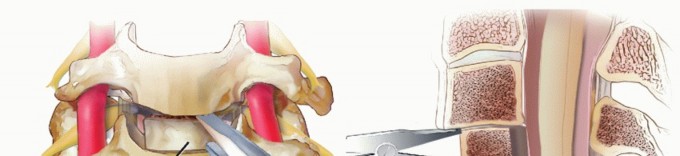

TECH FIG 3 • Anterior foraminotomy. A. The burr is used to thin down bone in the lateral aspect of the canal (arrow) until only a thin shell is left. The PLL is left intact as a protective layer to the neural elements until burring is completed. B. A curette is used to outline the bony edges and ensure that they are thin enough for passage of a curette or Kerrison rongeur. The PLL does not necessarily need to be resected during foraminotomy if the pathology is due solely to uncinate bone spurs, although we routinely do so and do not consider the decompression complete until the lateral edge of the dura and the exiting root are clearly visualized and palpated to be free of compression. C. A 2-mm Kerrison is then used to remove bone spurs. It is critical to hug the posterior margin of the uncinate during this move to avoid injuring the root underneath, which exits the canal ventrolaterally at about 45-degree angle. Note also that the vertebral artery is typically at the level of the mid-disc space. Thus, it is important to stay posterior when removing osteophytes off of the uncus rather than straying anteriorly where the vertebral artery is at greater risk. Constant irrigation is performed to prevent thermal injury and to clear away bone debris. If visualization is adequate, continued thinning of the osteophyte can progress until only a thin shell of bone is left. A microcurette or 2-mm Kerrison is then used to resect the thinned osteophytes. Alternating between microcurettes or a Kerrison and the burr, the foramen can be gently and progressively carved out laterally. The nerve root exits the spinal canal at roughly 45-degree angle ventrolaterally. Thus, it is imperative to avoid blindly placing a burr, curette, or Kerrison deep to the uncinate to avoid root injury. Instead, one should closely hug the uncinate while entering and decompressing the foramen (see FIG 1). Foraminotomy is complete when a micro nerve hook or curette can easily be passed into the foramen anterior to the exiting root without resistance.6 ### When and How to Resect the Posterior Longitudinal Ligament With soft disc herniations, a defect in the PLL is often present through which the nuclear material extrudes (TECH FIG 4A,B).